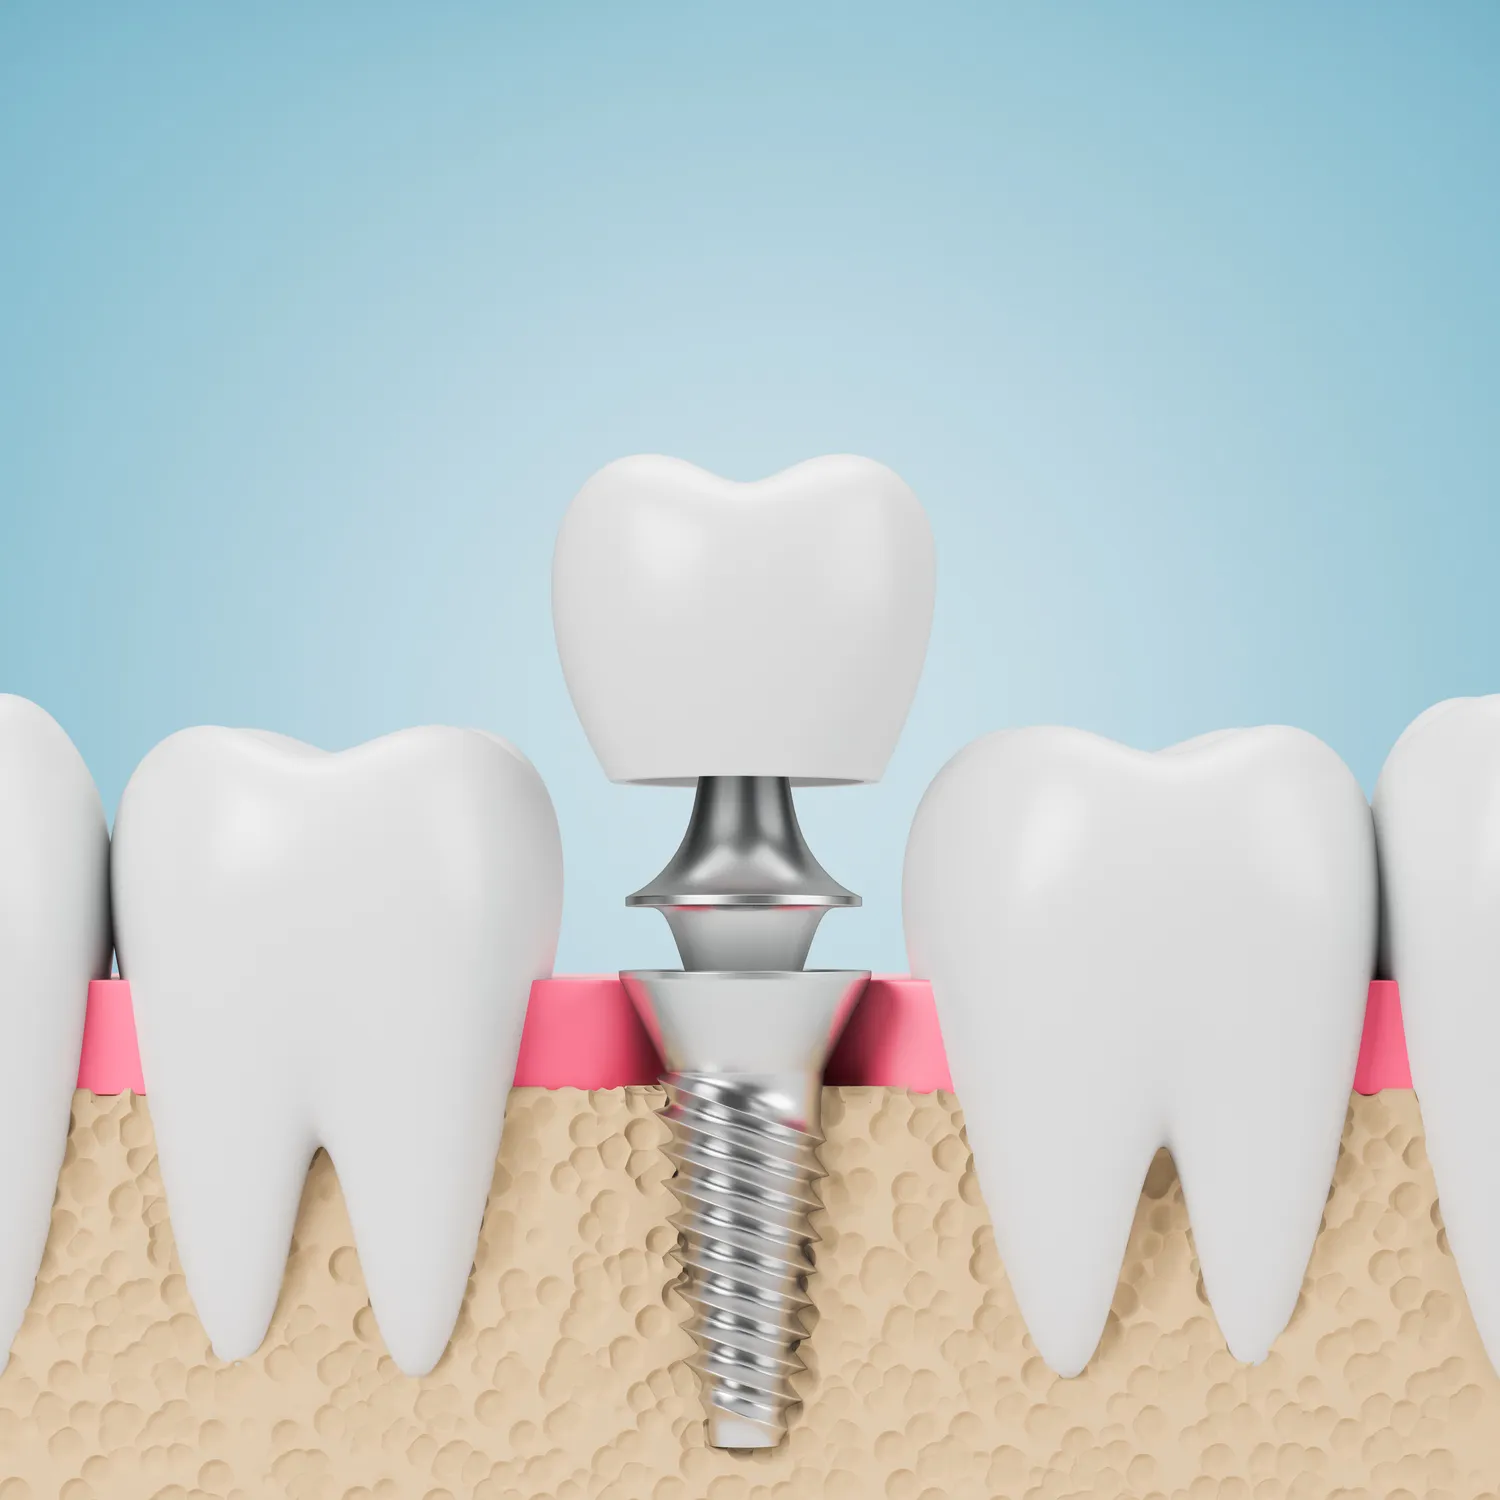

Cena implantów zębów jest uzależniona od wielu czynników, które warto znać przed podjęciem decyzji o ich wszczepieniu. Przede wszystkim istotna jest jakość materiału używanego do produkcji implantów oraz technologia ich wszczepiania. Implanty wykonane z tytanu są najczęściej stosowane ze względu na swoją biokompatybilność i trwałość. Kolejnym czynnikiem wpływającym na cenę jest doświadczenie i kwalifikacje stomatologa przeprowadzającego zabieg. Specjaliści z wieloletnim doświadczeniem mogą pobierać wyższe stawki za swoje usługi, co często przekłada się na jakość wykonania zabiegu oraz opiekę pooperacyjną. Również lokalizacja kliniki ma znaczenie – placówki znajdujące się w dużych miastach zazwyczaj mają wyższe ceny niż te w mniejszych miejscowościach. Dodatkowo warto zwrócić uwagę na koszty związane z diagnostyką i planowaniem leczenia, które mogą obejmować zdjęcia rentgenowskie czy tomografię komputerową.

W ostatnich latach rozwój technologii w dziedzinie implantologii zębów znacząco wpłynął na jakość i bezpieczeństwo zabiegów. Nowoczesne metody, takie jak cyfrowe planowanie leczenia, pozwalają na precyzyjne zaplanowanie każdego etapu wszczepienia implantu. Dzięki zastosowaniu tomografii komputerowej możliwe jest uzyskanie trójwymiarowego obrazu kości, co umożliwia dokładne określenie miejsca wszczepienia implantu oraz ocenę jego stabilności. Wprowadzenie technologii CAD/CAM do produkcji koron i mostów protetycznych pozwala na szybsze i bardziej precyzyjne wykonanie uzupełnień protetycznych. Dodatkowo, techniki takie jak implanty natychmiastowe, które można wszczepić w tym samym dniu co ekstrakcja zęba, stają się coraz bardziej popularne. Dzięki temu pacjenci mogą cieszyć się nowym uśmiechem w krótszym czasie. Warto również wspomnieć o zastosowaniu materiałów biokompatybilnych, które minimalizują ryzyko odrzutu implantu przez organizm.

Proces gojenia po wszczepieniu implantu zębów jest kluczowym etapem całego leczenia i może trwać od kilku tygodni do kilku miesięcy w zależności od indywidualnych warunków pacjenta oraz zastosowanej metody leczenia. Bezpośrednio po zabiegu pacjent może odczuwać dyskomfort lub ból w okolicy implantu, dlatego lekarz zazwyczaj przepisuje leki przeciwbólowe oraz antybiotyki w celu zapobiegania infekcjom. W pierwszych dniach po operacji ważne jest przestrzeganie zaleceń lekarza dotyczących diety – zaleca się spożywanie miękkich pokarmów oraz unikanie gorących napojów i alkoholu. Po kilku tygodniach następuje proces osteointegracji, czyli łączenia się implantu z kością szczęki, co jest kluczowe dla jego stabilności. Regularne wizyty kontrolne u stomatologa są niezbędne do monitorowania postępów gojenia oraz oceny stanu zdrowia jamy ustnej.